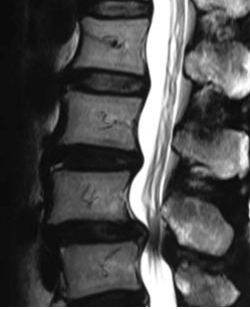

IMAGING STUDIES

Has imaging studies showed grade 1 degenerative spondylolisthesis L45 with moderately severe subarticular and subarticular stenosis at L5S1 and L34.